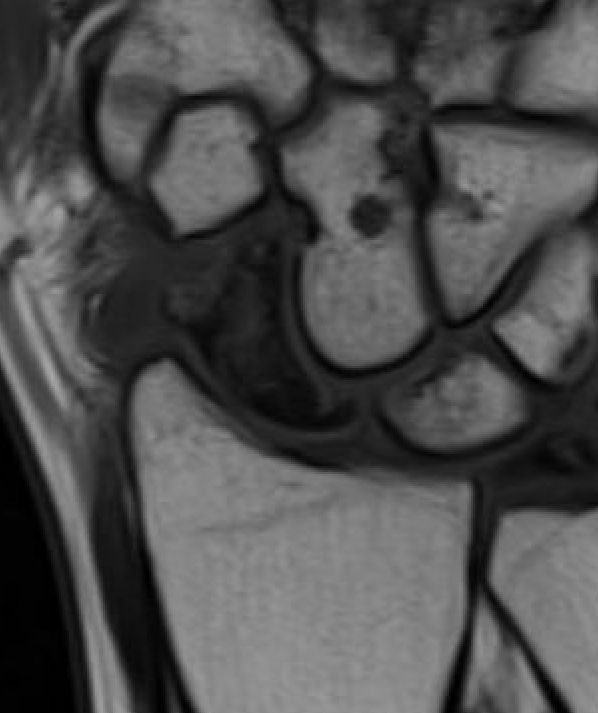

MRI

Low vascularity of scaphoid on T1 MRI and reduced gadolinium uptake proximal pole scaphoid